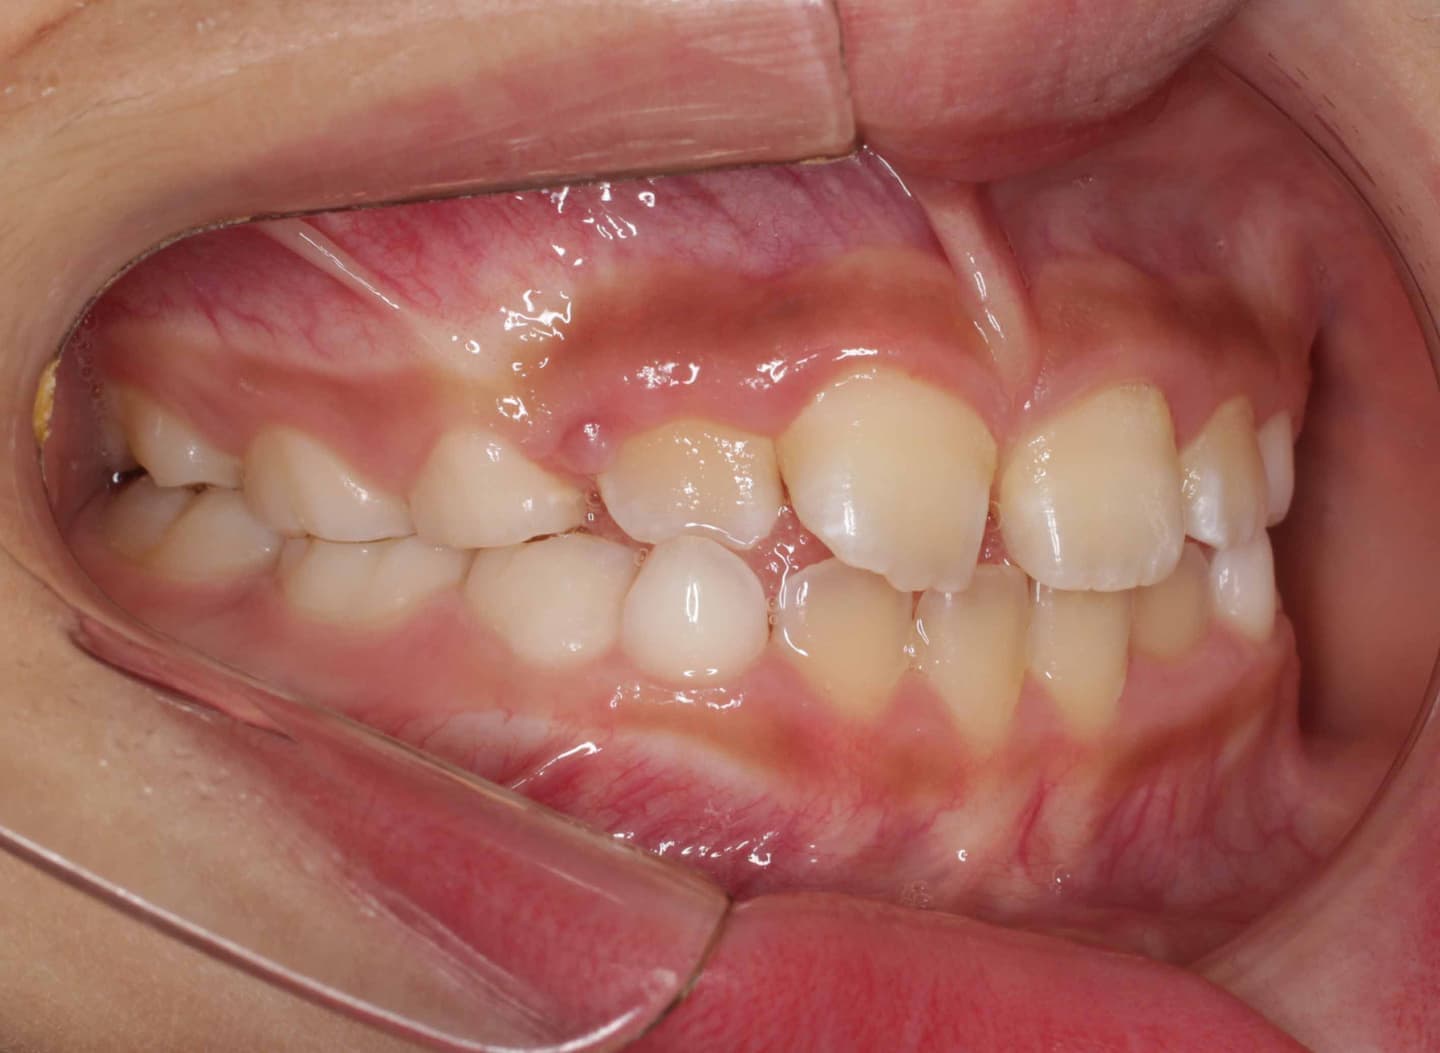

診断:初診時では右上3番の萌えるスペースがほとんどなく、顔と上顎と下顎の正中に対して、上顎前歯の正中が右にずれこんでいます。その影響で右上2番が右下乳歯Cと反対咬合になっています。放置すると、右上3番が埋伏歯になり、下顎の成長が左方向に流れるので、成長とともに顔面の非対称が増悪されることが予測されます。

治療前

右上乳犬歯が既に脱落しており、右上犬歯の萌出スペースがゼロになっています。